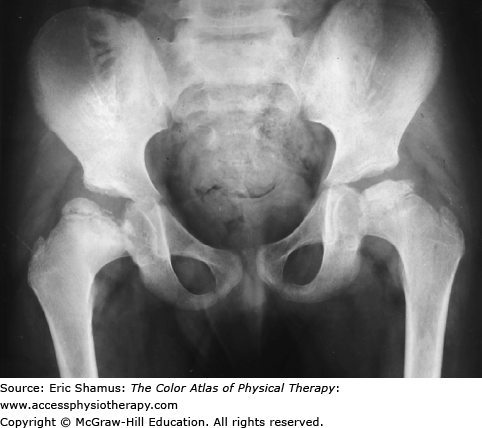

LEGG-CALVE-PERTHÉS DISEASE

An 11-year-old male is referred to physical therapy with a diagnosis of Legg–Calvé–Perthes disease (LCPD). Gait analysis reveals an antalgic gait on the affected left side. The child reports 7/10 pain in the hip and groin and difficulty with ambulation and stair climbing. His passive range of motion (ROM) is limited in left hip internal rotation, abduction, and extension. The parents report use of a Scottish-Rite brace was unsuccessful and the child is scheduled for surgical correction. The physical therapist instructs the child in crutch training pre-op and then provides gait training, RMO exercises, and strengthening post-op.

Answer with rationale: A. Hip Avascular Necrosis (AVN) with possible pathogenesis of injury, synovitis, infection or vascular abnormalities (either inherited or developed). AVN is the basic cause for LCPD, and it can develop from congenital or acquired sources. The AVN leads to destruction/degradation of the hip joint and surrounding structures, including necrosis and deformation. These in turn can lead to the symptoms noted in the patient: antalgic gait, pain, and limited mobility.